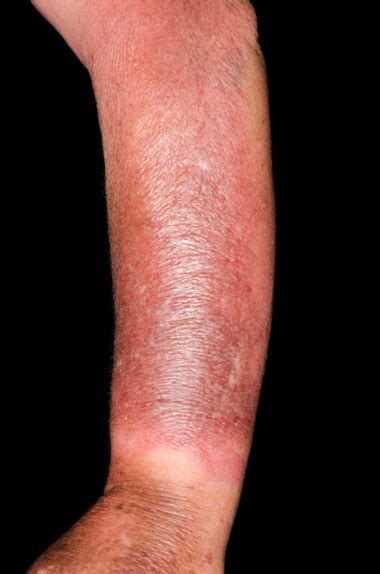

· Cellulitis is a bacterial infection of the skin and tissues beneath the skin. Learn more about its causes, symptoms, treatments, home remedies and complications. · To give you a better understanding of how cellulitis progresses, we have compiled a series of pictures that illustrate its stages. Please note that these images are for educational purposes only and should not replace a professional medical diagnosis. What does cellulitis look like?Here are some pictures of what cellulitis can look like. In some cases of severe cellulitis, an abscess (collection of pus) can also form, as shown below. Cellulitis rash on the leg on a darker skin tone. Close-up of cellulitis on the face. Close-up of cellulitis on a hand with an abscess. Which antibiotics treat cellulitis?Is cellulitis a skin infection?Cellulitis is a skin infection that comes on quickly. While some bacteria live on the skin at all times and are generally harmless, they can cause infection if they enter the skin. If you notice any swelling, redness, pain, or heat at a site where you’ve had a wound, contact your healthcare provider.How do you know if you have cellulitis?When cellulitis sneaks in around the toes, the skin can get dimply—like the surface of an orange peal. On darker skin tones, look for swelling, heat, or tenderness instead of classic redness. Want specifics? Take a peek at pictures of cellulitis on foot .Where does cellulitis develop?Most commonly, cellulitis develops in the area of a break in the skin, such as a cut, small puncture wound, or insect bite. It may also appear in the skin near ulcers or surgical wounds. In some cases when cellulitis develops without an apparent skin injury, it may be due to microscopic cracks in the skin that are inflamed or irritated. Detailed illustration, split view with cellulitis showing redness and glossy skin on the left, and skin abscess with raised appearance and pus on the right, clinical labels. Compare picturesofcellulitis and abscesses to understand their differences for proper treatment. · Cellulite is dimpled skin caused by fatty deposits. Cellulitis is a painful skin infection that happens when bacteria enter a break in your skin. · Cellulitis is a common, treatable skin infection but it can lead to serious complications. See picturesofcellulitis and learn the causes and treatment. · Cellulitis is a bacterial infection of the skin and tissues beneath the skin. Learn more about its causes, symptoms, treatments, home remedies and complications. · To give you a better understanding of how cellulitis progresses, we have compiled a series of pictures that illustrate its stages. Please note that these images are for educational purposes only and should not replace a professional medical diagnosis. Detailed illustration, split view with cellulitis showing redness and glossy skin on the left, and skin abscess with raised appearance and pus on the right, clinical labels. Compare picturesofcellulitis and abscesses to understand their differences for proper treatment.